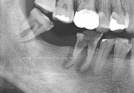

• Case1

• Case2

• Case3

• Case4

• Case5

• Case6

• Case7

• Case8

• Case9

• Case10